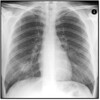

What pathology is seen here?

A

Cystic fibrosis

Lung looks scratchy